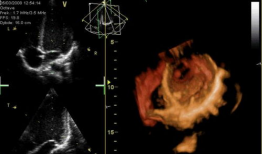

心脏跳动的视频,揭秘心脏跳动的奥秘

你知道吗?最近在网上流传着一个特别神奇的视频,它记录了心脏跳动的瞬间。这可不是普通的视频,它让我们仿佛能感受到心跳的力量,那种感...